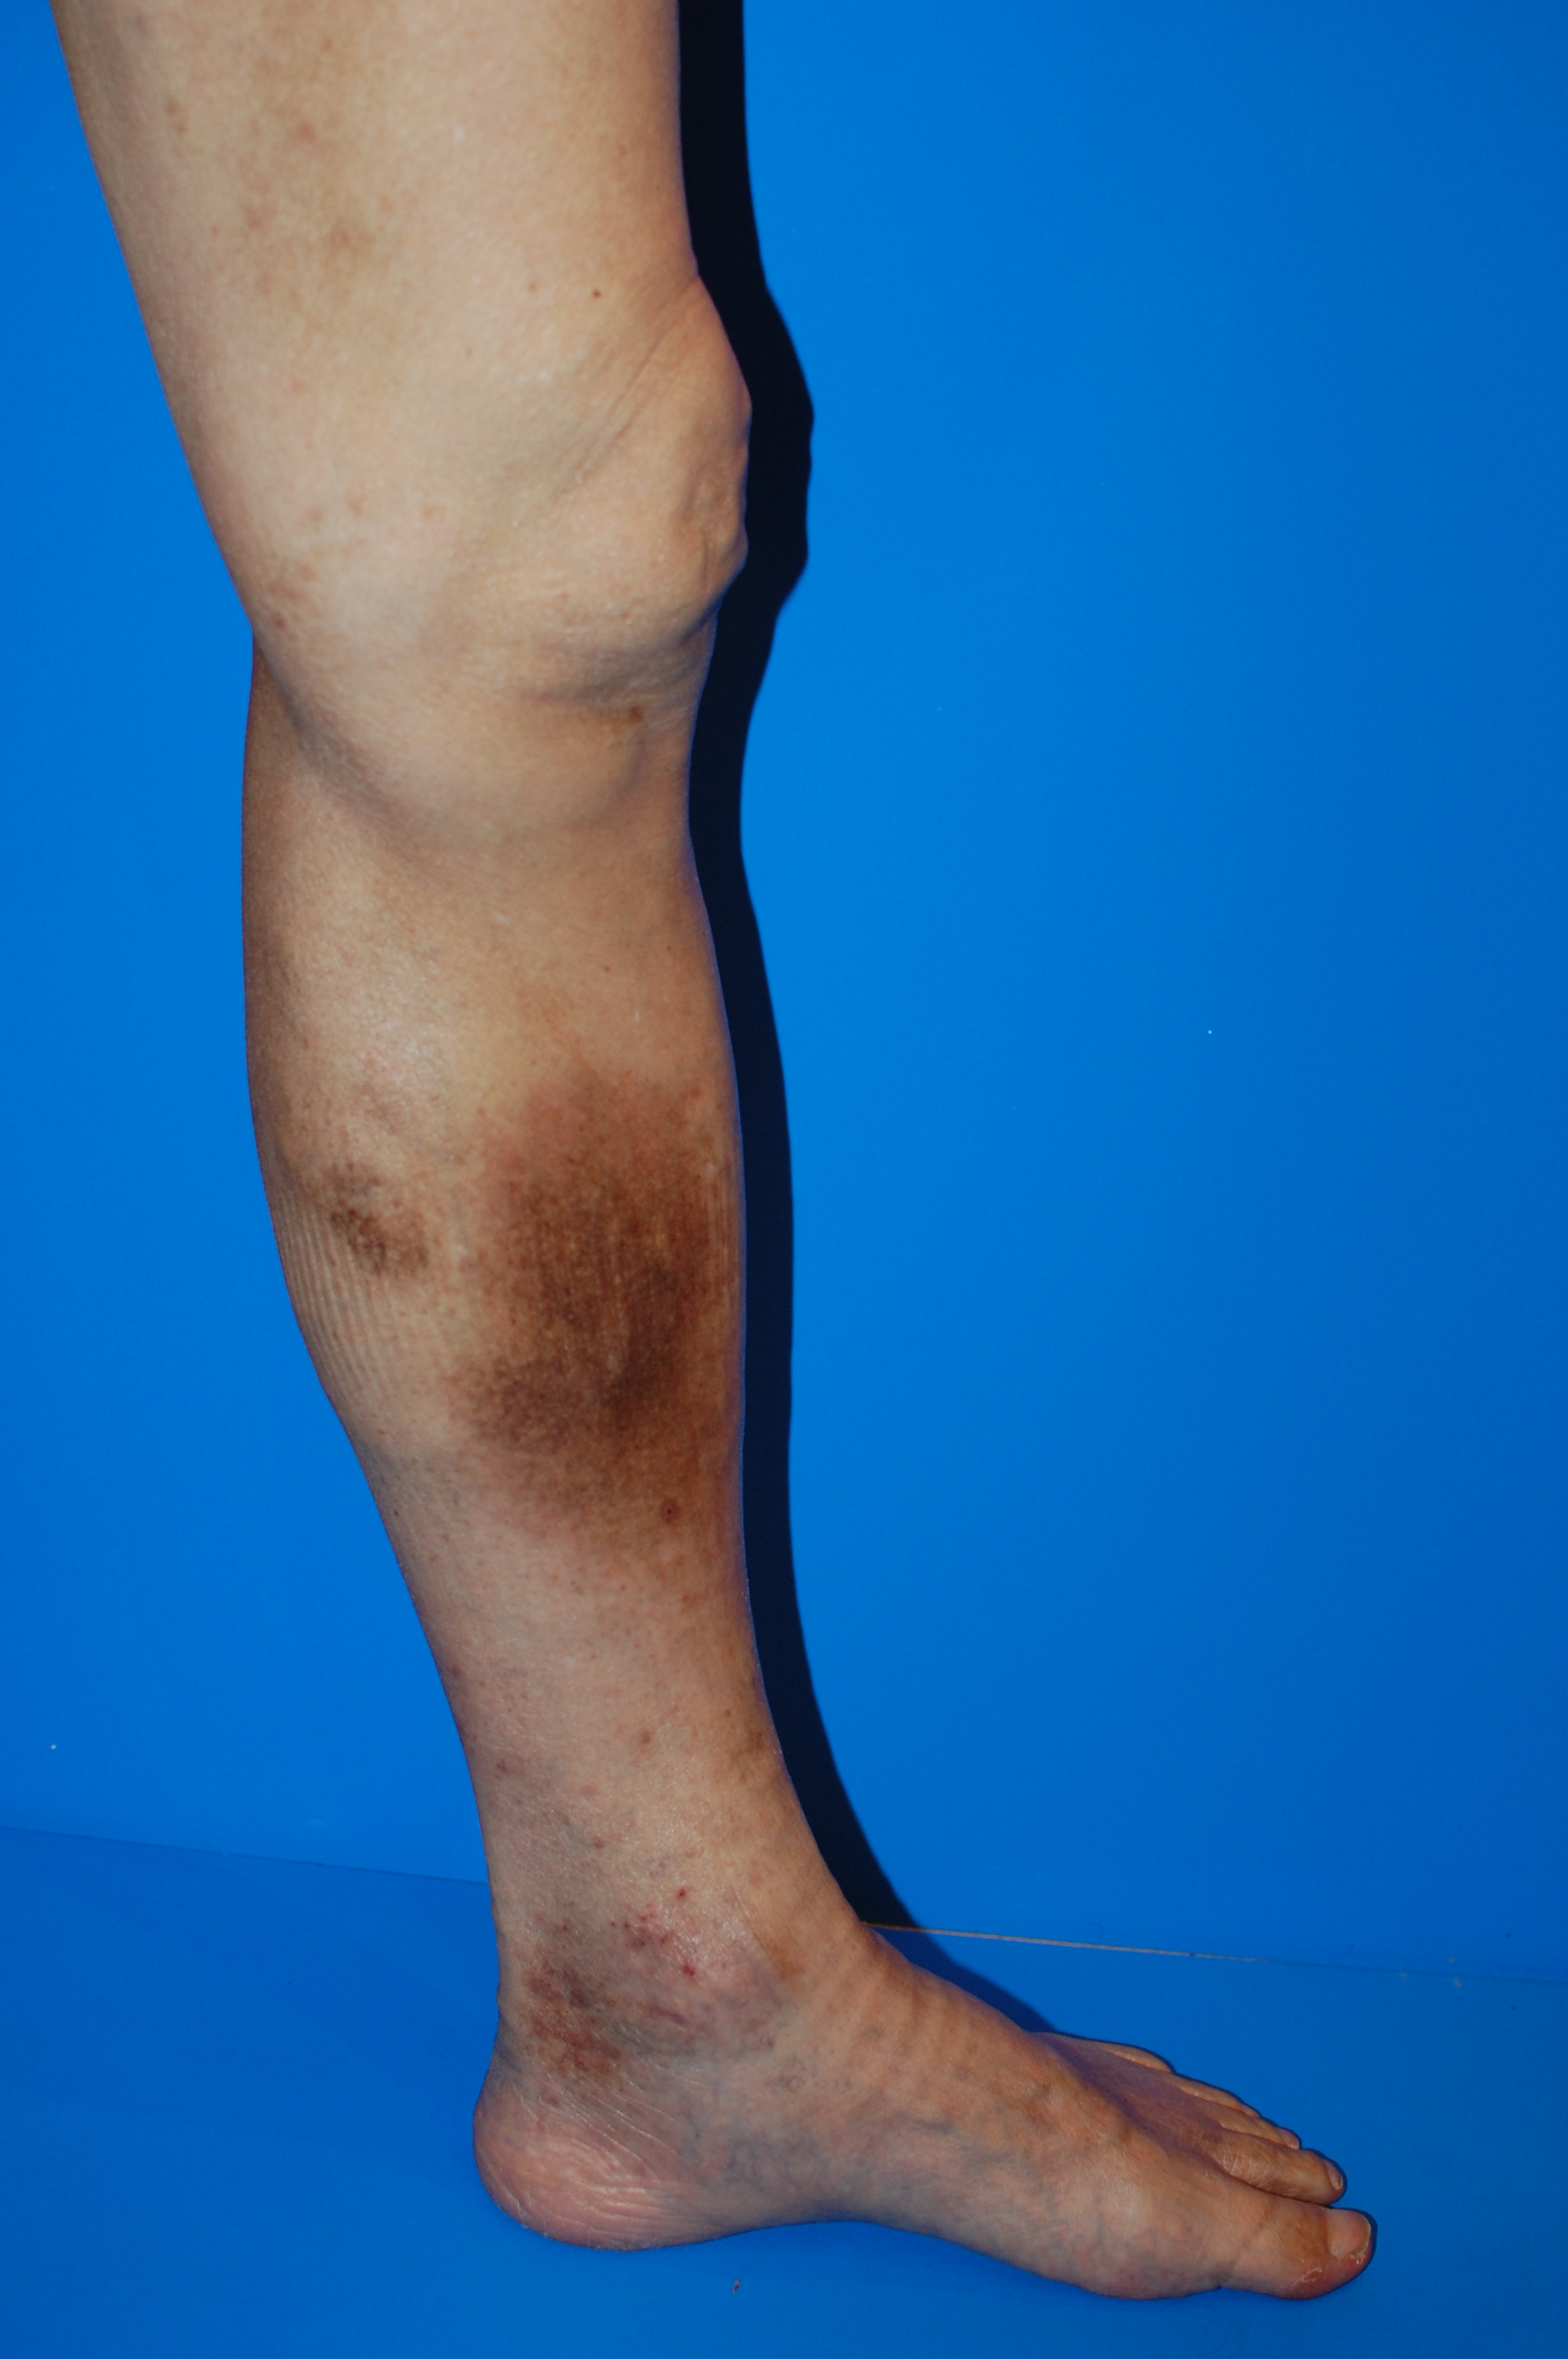

【ステップ2】色素沈着 ― 足首まわりが茶色く染まるサイン

これは、静脈瘤が単なる“血管のふくらみ”から“皮膚そのものの病気”へ進みつつある兆候です。

- 足首やすねの色が茶〜黒色に変化する

- 皮膚が厚く硬くなってくる

- 軽い痛みを感じることがある

下肢静脈瘤 色素沈着

色素沈着は改善しにくく、治療後も完全に元に戻らないことがある段階です。

見た目の悩みとして残りやすいため、ここに到達する前に対処するのが理想的です。